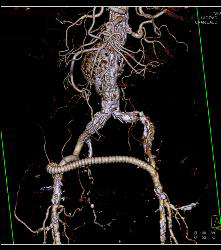

CTA Runoff With Occluded Left Popliteal Artery